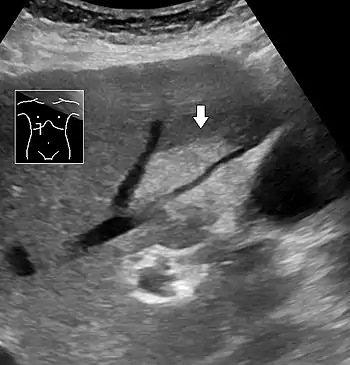

Abdominal ultrasonography of focal steatosis. It is distinguished from a tumor by not compressing the hepatic vein.